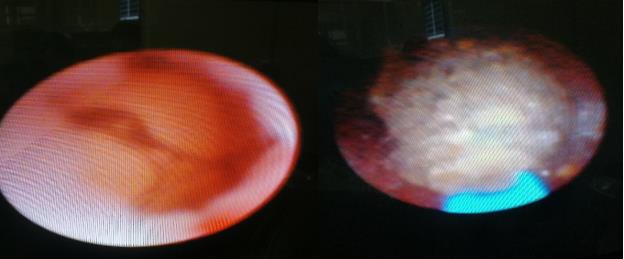

術(shù)前CT檢查:

右輸尿管結(jié)石 左輸尿管結(jié)石